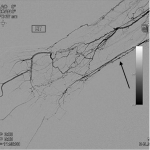

DIGITAL SUBTRACTION ANGIOGRAPHY (DSA)

The following gallery shows examples of Buerger disease seen on DSA studies. Click the thumbnails below to open up the gallery.